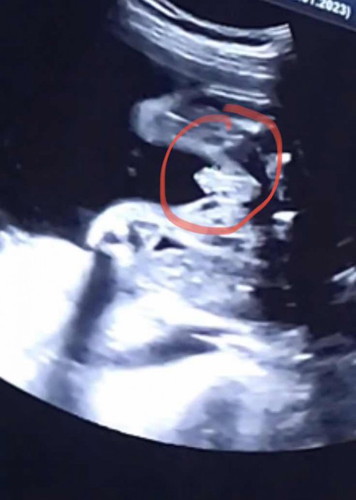

Gender baby

Hi mommies, last week scan scan jelas dia tunjuk dia punya pistol, so confirm boy kan ? Risau tiba2 nnti ada plot twist pulak dah keluar 😅

Sy pun scan nampak pistoll 25week..dah 2kali scan nmpk pistol..😍

Boy sis. Moga diprmudhkn. Klau line burger tu girley la tu hee